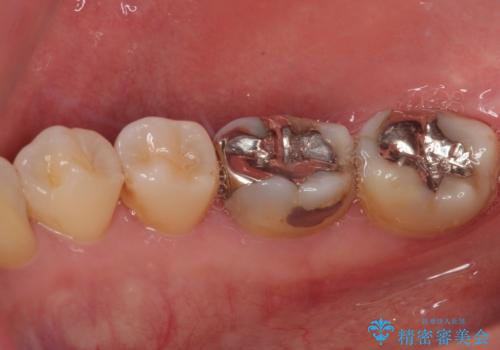

- 当院で矯正後に銀歯が目立つのでやり替えたいと来院された患者様です。銀色の詰め物(メタルインレー)と歯の間に隙間を認め、あまり歯を削りたくないとのことで患者様と相談の結果右下の7番目の歯はセラミックインレー、右下の6番目の歯はメタルインレーが大きいためフルジルコニアクラウンでの治療を行うことになりました。

拡大鏡視野下で、銀色の詰め物(メタルインレー)、保険のプラスチック、虫歯の除去を行い、セラミックインレー、フルジルコニアクラウンに適した形に整えました。